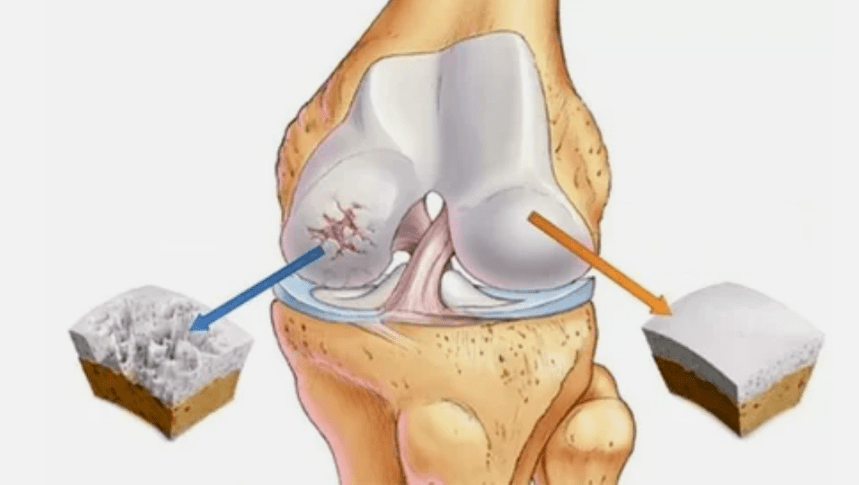

- Patoloxías de revestimento de hialina. O adelgazamento da cartilaxe leva á substitución dos seus tecidos patolóxicos - estruturas óseas.

- Os crecementos anómalos aparecen na cartilaxe - osteófitos.

- A derivada violación da anatomía natural da cartilaxe e os ósos provoca a sobrecarga de zonas saudables de cartilaxe. A destrución de tecidos articulares sen tratamento está a avanzar constantemente e levar a discapacidade.

Cando aumenta o grao de enfermidade, os procesos patolóxicos aínda se agravan. Ao final, toda a cartilaxe de hialina é destruída.